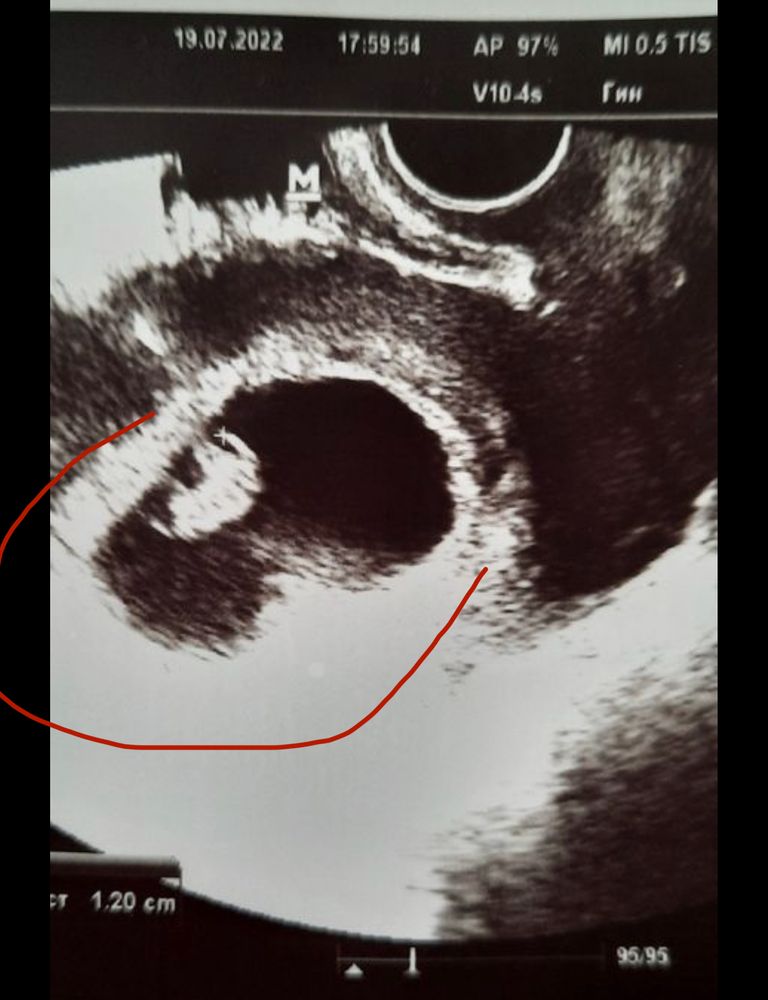

Добрый день,милые беременюшки!Ну вот я снова с вами, хотя уже думала,что на третьем сынуле остановлюсь....но вот судьба решила иначе.Первый раз без приёма гормонов,без подготовки к беременности,Бог наградил нас ещё одной пуговкой)))Помогите,пожалуйста, определить кого на этот раз ждём, мальчика или девочку по методу Рамзи?Узи на 7-8 недели беременности, трансвагинально

Не понятно где большая часть хориона по правой или левой стороне) вроде слева, если слева мальчик